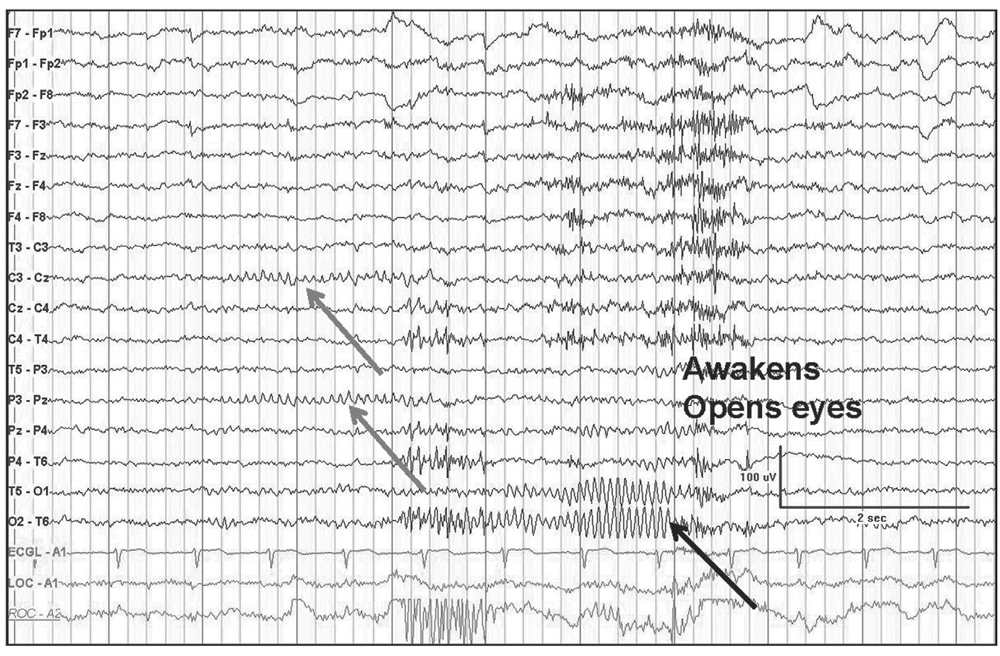

In some cases, it is not possible to determine the normality or abnormality unless a previous EEG is available for comparison. The normal low-voltage background pattern also tends to show well-defined and prominent photic driving responses with high-frequency photic stimulation. The measurable alpha rhythm may also appear during hyperventilation. In some normal people, the background activity is low voltage initially but may show measurable alpha rhythm in the latter portion of the recording. It doesnt show if theres any damage or physical abnormalities in your brain. 6 In some cases, it is difficult to differentiate if the low-voltage activity is abnormally Abnormal EEG Patterns correlation with underlying cerebral lesions and neurological diseases Suthida Yenjun Definition of the abnormal EEG An EEG is abnormal if it contains Epileptiform activity Slow waves Amplitude abnormalities or Deviations from normal patterns In most abnormal EEGs, the abnormal patterns appear only. An EEG test only gives information about the electrical activity in your brain. 5 There is some evidence that genetic factors play a role in determining the voltage pattern in a healthy person. The two main types of slowing are focal and generalized slowing. EEG can provide evidence for underlying diffuse or focal cerebral dysfunction through demonstration of background slowing.

Approximately 10% of normal subjects show a low-voltage (<20 µV) background pattern that is difficult to measure. The Abnormal EEG - Electroencephalography (EEG): An Introductory Text and Atlas of Normal and Abnormal Findings in Adults, Children, and Infants - NCBI Bookshelf.